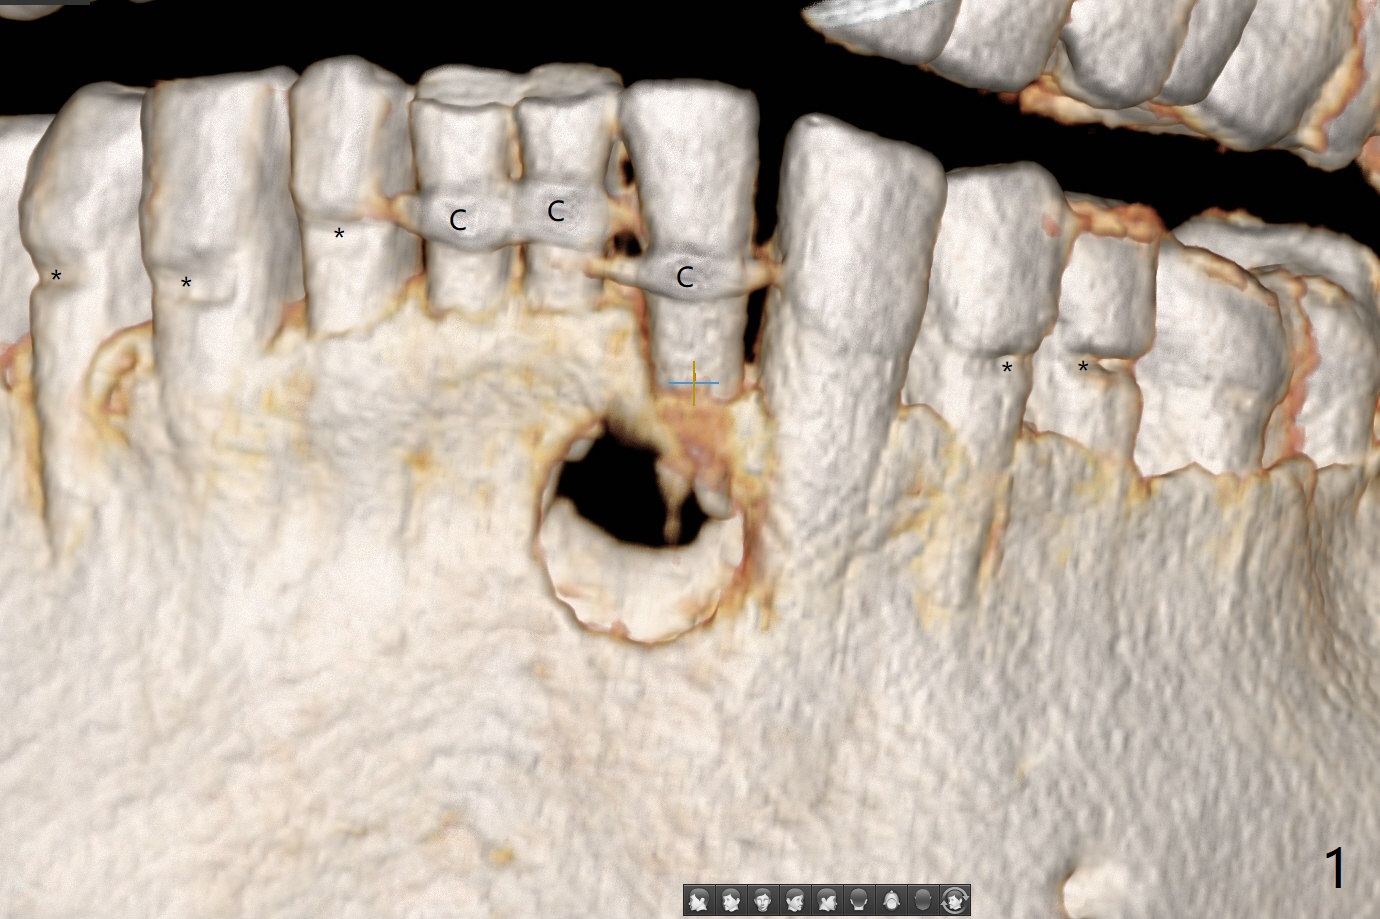

A 73-year-old woman has discomfort associated with #23 four months post Class V composite at #23-25 (Fig.1 C (*: Class V lesions)). Bone loss seems to be more severe lingually, especially at the crest (Fig.2 L). It appears that the apex of the tooth #24 is also in the large apical lesion (Fig.3). Class V composite is apparently continuous with the pulp at #25,24,23 (Fig.5-7). In contrast, Class V defect does not involve the pulp at #26 (Fig.4). If necrosis is confirmed clinically for #23 24 and 25, RCT will be conducted. Due to 7-day Amoxicillin taken for #3 implant, the patient feels that her tongue moves freely, as related to reduction in pain and swelling lingual to #23 (Fig.8 *). Endo ice test shows necrosis of #23 to 25. RCT is initiated at #23 (Fig.9) with buccal and lingual swelling. Endo may have to be at #24 with apicoectomy with PRF. The lingual swelling remains at #23, although there is no pain or purulent discharge 5 and 5.5 months post debridement (Fig.10,11). RCT is finished (Fig.12). Apicoectomy is pending with PRF. Less aggressive curettage will be done at #24 to maintain apical blood supply. Vitality tests have been done without conclusion.